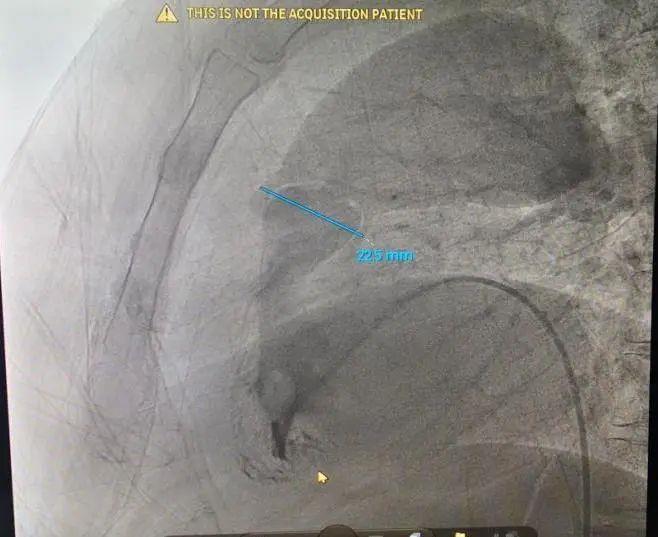

造影显示肺动脉瓣部位及测量瓣环直径